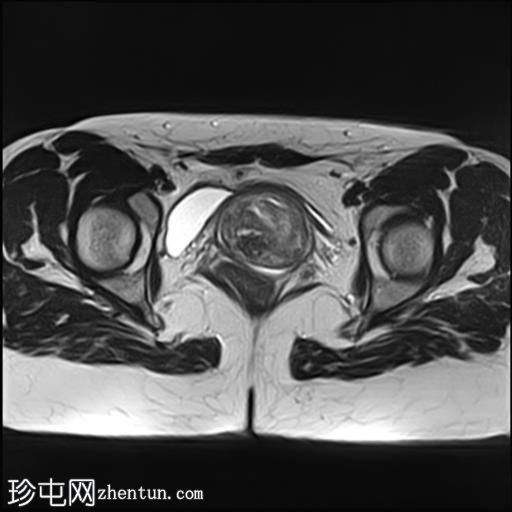

冠状位

T2加权像

子宫增大,前倾后屈,可见多发大小不一、位置各异的壁内肌瘤(主要位于Figo 2、5和6区)。

一个边界清晰的带蒂宫腔内肿块经扩张的宫颈管脱出。T1加权像上呈等信号,T2加权像上呈中低信号,周围环绕着高信号的子宫内膜,静脉注射对比剂后呈明显不均匀强化。

双侧卵巢外观正常,可见小卵泡。

MRI 影像特征最符合带蒂子宫肌瘤经扩张的宫颈管脱垂,并伴有多个子宫肌瘤。